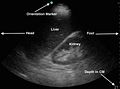

Siêu âm là kỹ thuật chẩn đoán hình ảnh bằng cách sử dụng sóng siêu âm (sóng âm tần số cao) để xây dựng và tái tạo hình ảnh về cấu trúc bên trong của cơ thể.